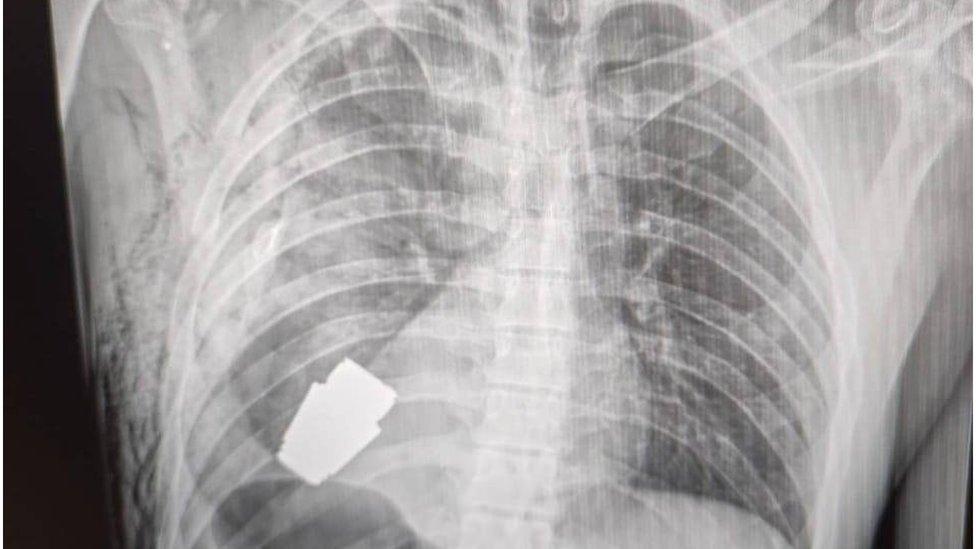

గాయపడిన జవాన్ ఛాతి లోపల ఇరుక్కుపోయి, ఎప్పుడైనా పేలిపోయే స్థితిలో ఒక చిన్న గ్రెనెడ్ను వారు విజయవంతంగా బయటకు తీశారు.

జవాన్ శరీరంలోని గ్రెనెడ్ 4 సెం.మీ వ్యాసార్థంతో, 275 గ్రాముల బరువుతో ఉంది. ఇది రష్యా వీఓజీ ప్రాంగ్మెంటేషన్ గ్రెనెడ్.